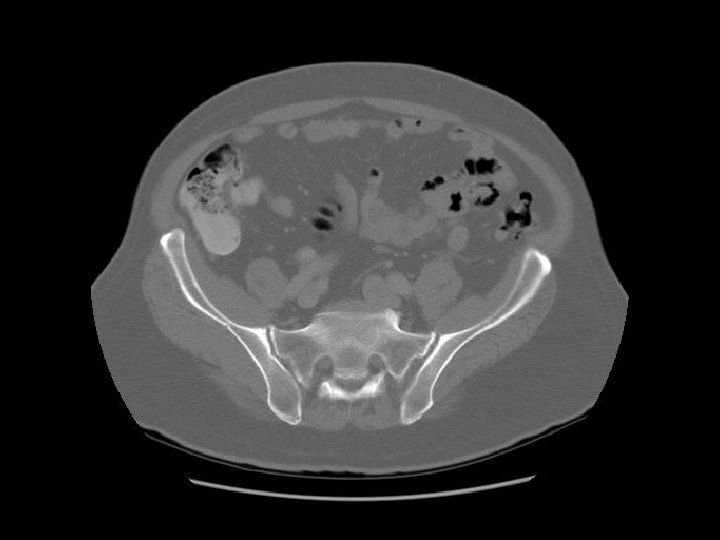

Arrows are pointing to the common iliac veins joining to form the IVC. Left

Ilium Sacrum

Arrows are pointing to the internal and external iliac veins joining to form the common iliac vein.